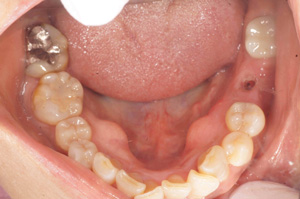

@@R.S‚³‚ñ@56Î —«  ‘åŠw‹³Žö @Žèp“ú@‚Q‚O‚O‚W”N ‚QŒŽ ‚X“úi“yj@㉺Š{  ƒm[ƒxƒ‹ƒKƒCƒhŽg—p@Ö¬“à’ÁÖ@•¹—p@@@

@@@@@ãŠ{  All on ‚U@‘¦Žž‰Ád@@

@@@@@@@@@@@@@ Rpl Tapered Rp  ‚P‚O mm(‚U–{)

@@@@@‰ºŠ{¶‰E@‘¦Žž‰Ád@ ‚R Unit Bridge@

@@@@@@@@@@@ @Rpl Tapered Rp  ‚P‚O mm(‚S–{)@@–ƒWƒ‹ƒRƒjƒAƒNƒ‰ƒEƒ“‚ÅÅI•â’Ô